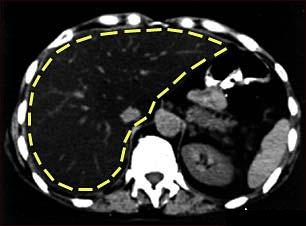

Steatohepatita nonalcoolica (NASH)